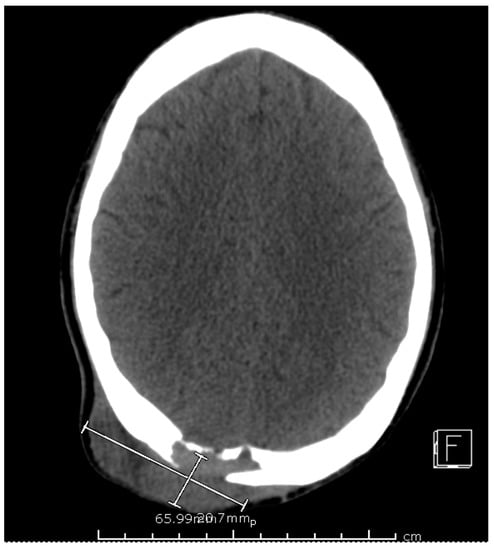

The computed tomography (CT) scan of his chest and abdomen revealed a right upper lobe cavitary lesion abutting the ribs (Figure 2) and a sinus tract from his left ischium to the skin over his left lower abdomen, respectively. Additionally, a CT scan of his head was also obtained, which demonstrated a mass extending from his right occipital skull with evidence of skull erosion as well (Figure 3).

Figure 3. CT scan of head, aggressive lytic lesion of the posterior right parietal bone with an associated 6.6 × 2.1 × 7.1 cm soft tissue mass of the posterior scalp.